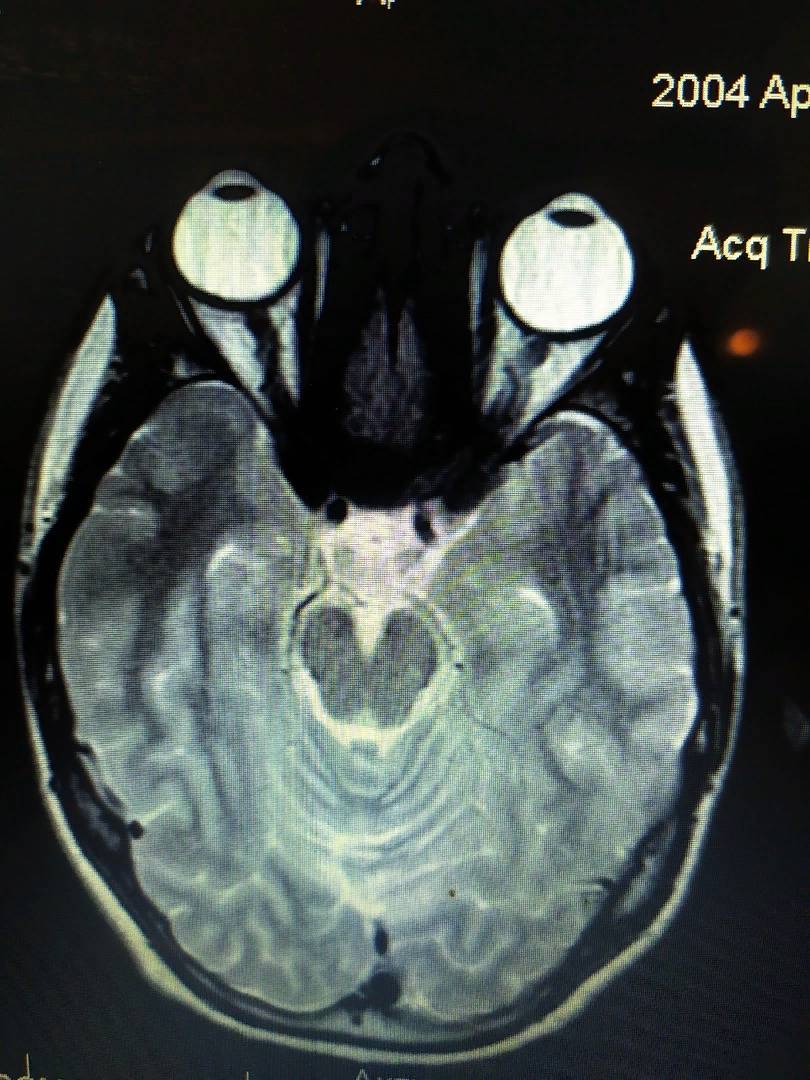

Ещё одна томография, которую мне прислал мой подписчик. Обратите внимание на то, что правый глаз заметно, но не сильно больше левого.

На правом глазу здесь -6.25 диоптрий. А на левом -4.5. Видите, разница не сильно большая, поэтому и глаза в длину не сильно отличаются (по сравнению с первой фотографией).

И опять заметьте, что глаза здесь не сдавлены глазодвигательными мышцами с боков. А они просто выросли и стали больше.